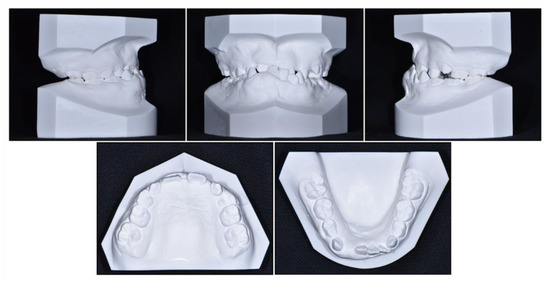

Intraoral examination showed anterior crossbite and severe deep bite with a −2.0 mm overjet and 7.0 mm overbite with no functional shift. The patient exhibited severe crowding on maxillary dentition along with a maxillary transverse deficiency. The mean difference in the width of the maxillary and mandibular first molars at the age of 8 years has been reported to be 6.4 mm, whereas in our patient, it was only 4 mm [19]. He showed a 1 mm deviation of the mandibular dental midline toward the left side. Hypertrophy of the mandibular right anterior alveolar bone was clear, which had led to the canting of the mandibular anterior teeth.

Figure 2. Pre-treatment cast models.